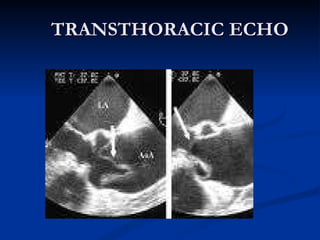

TRANSTHORACIC ECHO

TRANSESOPHAGEAL ECHO Procedure of first choice for dissection, if readily available Portability of equipment facilities in emergency to ER or ICU High sensitivity (98%) and specificity(97%)   Limitations : Unable to visualize distal part of asc. Aorta (beginning of aortic arch) and  desc. Aorta below stomach

TRANSESOPHAGEAL ECHO Procedureof first choice for dissection, if readily available Portability of equipment facilities in emergency to ER or ICU High sensitivity (98%) and specificity(97%) Limitations : Unable to visualize distal part of asc. Aorta (beginning of aortic arch) and desc. Aorta below stomach